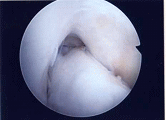

半月板部分切除術

(水平断裂合併)

(水平断裂は僅かに残存)

正常に見えるが